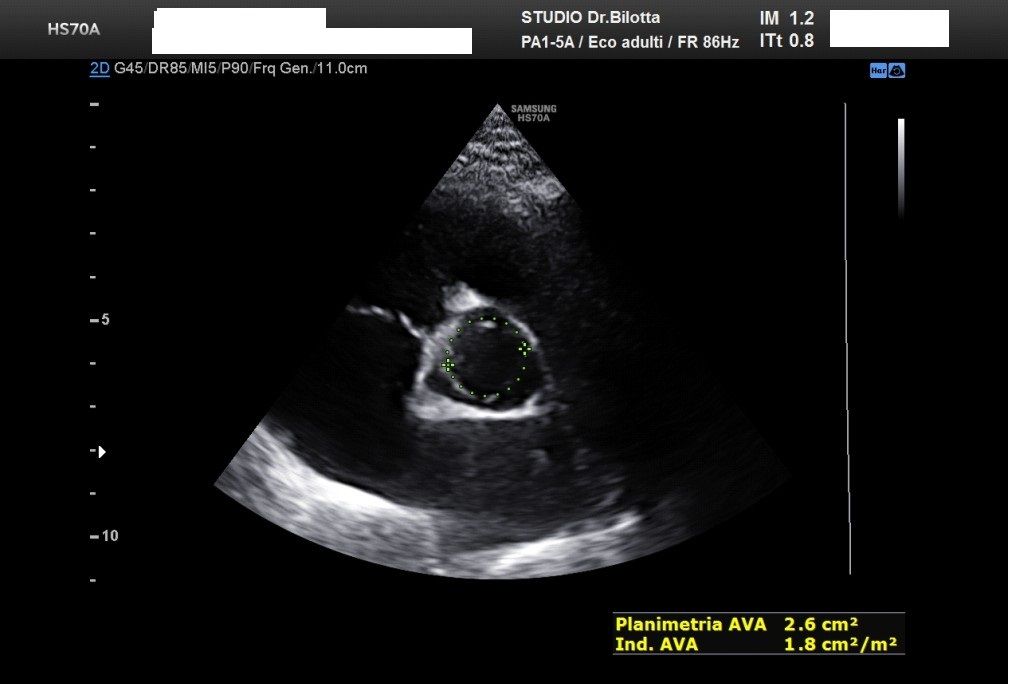

Diploma di maturità classica. Laurea in Medicina e Chirurgia con Lode a 26 anni. Specialista in Oncologia Generale Diagnostica e Preventiva con Lode a 31 anni. Specialista in Malattie Cardiovascolari a 36 anni. Medico generalista dal 1990 poi ospedaliero per trent'anni dal 1993 al 2022 nel corso dei quali ho refertato oltre 100 mila tracciati elettrocardiografici, effettuato oltre 30 mila consulenze specialistiche, praticato circa 10 mila esami ecocardiografici, condotto oltre 2 mila test ergometrici sia su cicloergometro che su treadmill, visionato circa 1500 esami Holter Ecg e ABP ( Ambulatory Blood Pressure ) occupandomi prevalentemente di prevenzione cardiovascolare, ipertensione arteriosa, cardiopatia ischemica, valvulopatie. Dal 2023 ho deciso di trasferire le mie competenze nella libera professione presso il mio studio privato che è stato allestito in linea alle moderne esigenze tecnologiche. Metodiche diagnostiche attualmente praticate: Elettrocardiografia a riposo, Ecocardiografia mono-bidimensionale, PW, CW, Colordoppler tridimensionale, GLS Strain Speckle tracking, Monitoraggio Holter Pressorio delle 24 ore, Monitoraggio Holter ECG 12 canali dinamico delle 24 ore.

Foto e video